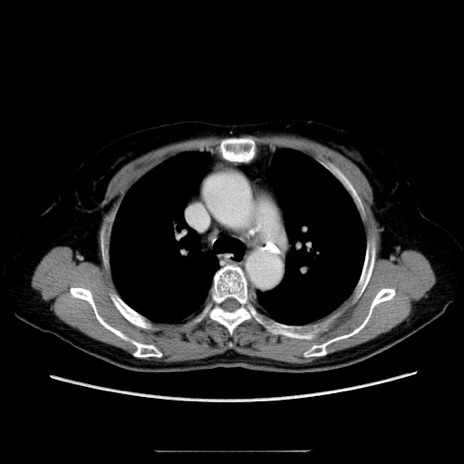

症例5(横断像)

【症例】70歳代女性

【主訴】お腹が張る

【現病歴】1週間くらい前から腹部膨満の自覚あり。昨日夜から増悪したため、本日救急外来受診。

【身体所見】意識清明、BT 36.5℃、BP 165/106mmHg、HR 80bpm、SpO2 98%、腹部:膨満、軟、自発痛・圧痛なし、触診にて不快感あり、腸蠕動音:減弱

【データ】WBC 12600、CRP 1.04